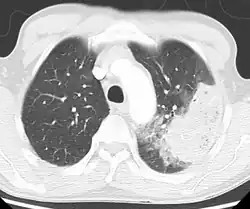

A chest radiograph is frequently used in diagnosis.[23] In people with mild disease, imaging is needed only in those with potential complications, those not having improved with treatment, or those in which the cause is uncertain.[23][69] If a person is sufficiently sick to require hospitalization, a chest radiograph is recommended.[69] Findings do not always match the severity of disease and do not reliably separate between bacterial and viral infection.[23]

X-ray presentations of pneumonia may be classified as lobar pneumonia, bronchopneumonia, lobular pneumonia, and interstitial pneumonia.[75] Bacterial, community-acquired pneumonia classically show lung consolidation of one lung segmental lobe, which is known as lobar pneumonia.[42] However, findings may vary, and other patterns are common in other types of pneumonia.[42] Aspiration pneumonia may present with bilateral opacities primarily in the bases of the lungs and on the right side.[42] Radiographs of viral pneumonia may appear normal, appear hyper-inflated, have bilateral patchy areas, or present similar to bacterial pneumonia with lobar consolidation.[42] Radiologic findings may not be present in the early stages of the disease, especially in the presence of dehydration, or may be difficult to interpret in the obese or those with a history of lung disease.[24] Complications such as pleural effusion may also be found on chest radiographs. Laterolateral chest radiographs can increase the diagnostic accuracy of lung consolidation and pleural effusion.[41]